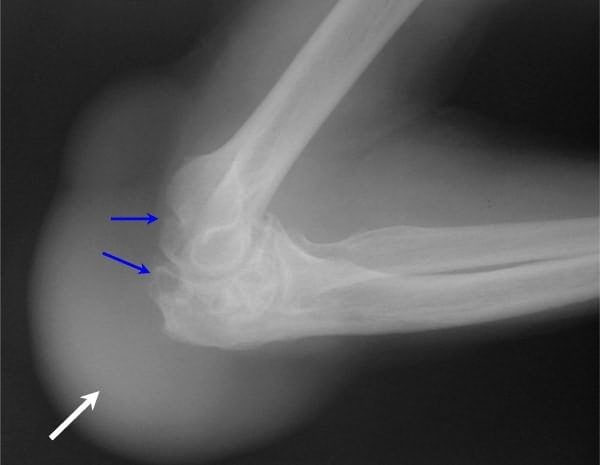

При остром и хроническом гнойном бурсите требуется проведение инструментальных исследований:

- рентгенографии;

- УЗИ;

- компьютерной или магнитно-резонансной томографии.

По результатам обследования устанавливается степень поражения сустава и количество развившихся осложнений.